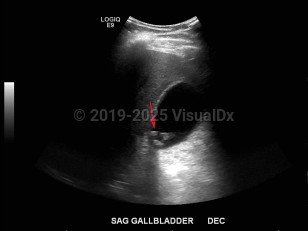

Hardened crystal deposits formed from bile pigments, cholesterol, and calcium salts found in the bile duct (choledocholithiasis) or gallbladder (cholecystolithiasis). Commonly called gallstones, they are characterized by severe right upper quadrant abdominal pain or epigastric pain due to transient obstruction of the biliary tract. Other symptoms include nausea, vomiting, hyperbilirubinemia, and elevated alkaline phosphatase and gamma-glutamyl transpeptidase.